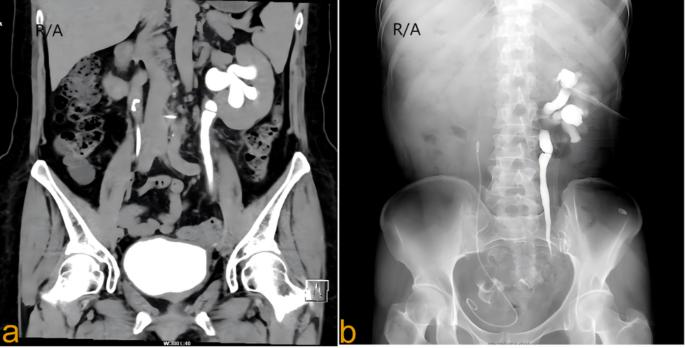

患者的CTU和顺行输尿管造影显示输尿管狭窄长度为80mm(图1a,b)。实验室和功能评估显示:SCR为172µmol/L;VAS评分为4分;KPS评分为60分;eGFR为29.98 ml/min。尿动力学评估显示膀胱容量为250 ml,最大尿流率为25 ml/s,逼尿肌压力为40 cmH2O.膀胱亚甲蓝试验结果为阴性。

图1 a CTU显示左输尿管上段扩张,盆腔段狭窄 b顺行输尿管造影显示左输尿管腹段扩张